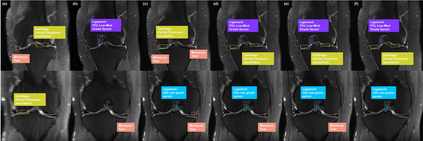

Score-based diffusion models provide a powerful way to model images using the gradient of the data distribution. Leveraging the learned score function as a prior, here we introduce a way to sample data from a conditional distribution given the measurements, such that the model can be readily used for solving inverse problems in imaging, especially for accelerated MRI. In short, we train a continuous time-dependent score function with denoising score matching. Then, at the inference stage, we iterate between numerical SDE solver and data consistency projection step to achieve reconstruction. Our model requires magnitude images only for training, and yet is able to reconstruct complex-valued data, and even extends to parallel imaging. The proposed method is agnostic to sub-sampling patterns, and can be used with any sampling schemes. Also, due to its generative nature, our approach can quantify uncertainty, which is not possible with standard regression settings. On top of all the advantages, our method also has very strong performance, even beating the models trained with full supervision. With extensive experiments, we verify the superiority of our method in terms of quality and practicality.